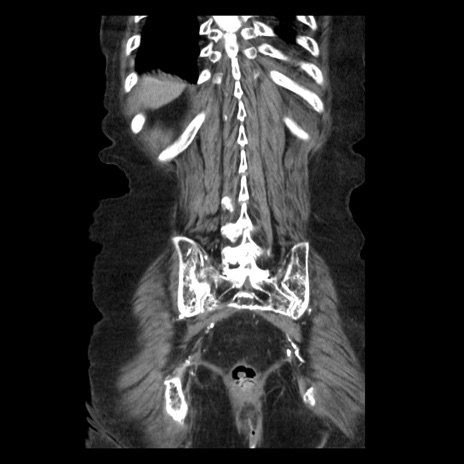

症例14(冠状断像)

【症例】 90歳代女性

【主訴】 腹痛・嘔吐

【現病歴】今朝から左側腹部痛を認めた。 経過観察していたが、嘔吐を認めたため来院。

【既往歴】 子宮癌術後

【身体所見】 意識清明、BP 127/54mmHg、P 98bpm Sp02 95%(RA)、BT 35.8°C、腹部平坦・軟腸ぜん動音聴取良好、右下腹部圧痛(+) 反跳痛なし

【データ】WBC 9800、CRP 0.46